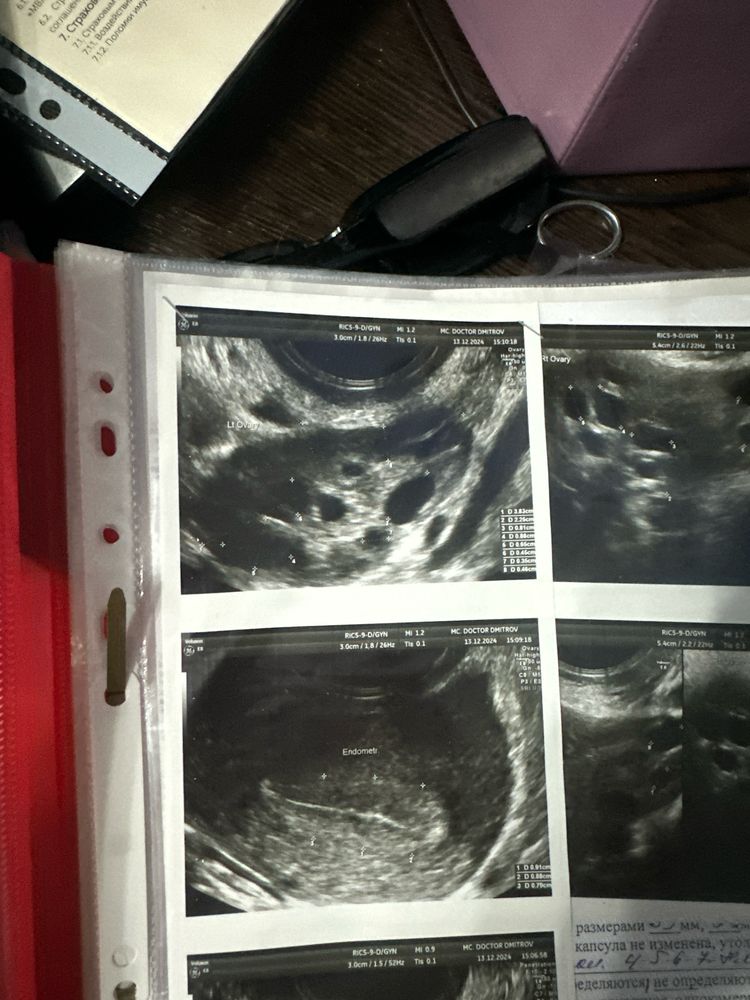

Здравствуйте ,подскажите пожалуйста у кого поликистоз. Как лечили ? Больше года не могу забеременеть, врачи ставили постоянно разные диагнозы . Попала к лучшему врачу в городе , поставили поликистоз. Сказали сдавать на гормоны . Матка 4 см и яичники тоже 4 см

узи прикрепляю

Яичники у вас вообще не поликистозные если честно. Спкя лечится 1 диета снижение веса + Физ нагрузки + инозитол, не поможет стимуляция овуляции вне эко, надсекают кору яичника но это опасно, если овуляции не дает кора случится и эко. Никакие прогестероны и кок и прочее … и Спкя синдром он не лечится. Но по узи это не Спкя как будто и нужны конечно гормоны и на фоликлометрии овуляцию ловить и спермограмму смотреть и трубы